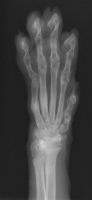

ところで、ミケりんの骨折から今日でちょうど4週間になりました。ギブスの生活に慣れるのか心配しましたが、意外にもギブスを取ろうとしたり気にしたりもなく「頼むから安静にしてくれ」ってぐらい活発に動くのでそっちの方が大変でした!

そして、ついにギブスをはずすことができました!

ナスビと言われていたギブス。キュウリもありました!小指が怪しいけどほぼくっ付いたかなぁ!